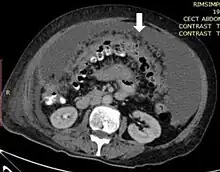

L'imagerie joue également un rôle clé dans la détection de la carcinose, l'évaluation de l'atteinte et la surveillance. Les modalités les plus performantes sont le scanner, l'IRM et le TEP scanner[9].